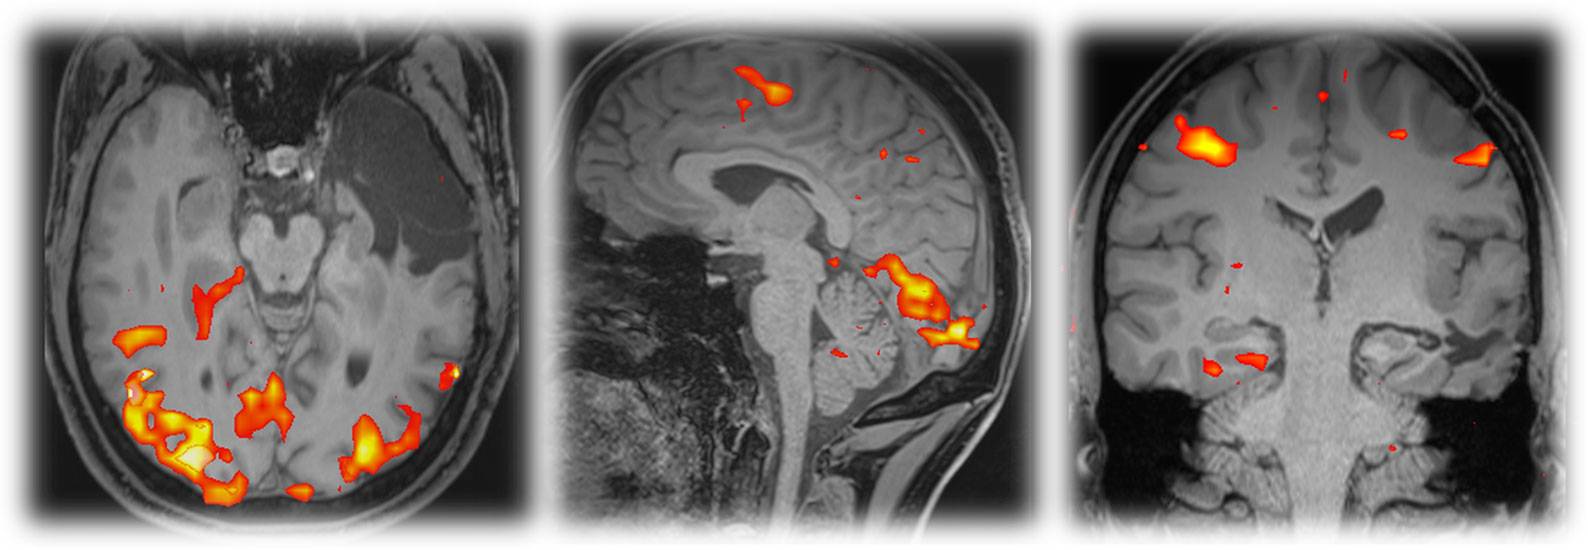

A 5-year-old male child presented with complaints of recurrent generalized tonic–clonic seizures and right-sided weakness ,predominantly involving the lower limb along with anger outbursts and abnormal behaviour.